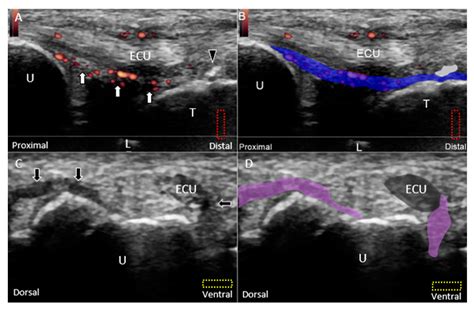

• Ultrasound: To evaluate the ligament's integrity and detect any tears or inflammation.